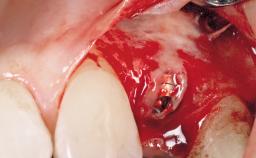

Immediate Flapless Placement of an Implant in a Maxillary Left Central Incisor Site

A 42-year-old female patient was referred to our clinic at the School of Dentistry of the University of São Paulo in November 2004, presenting a deficient restoration in the upper left central incisor. The clinical examination revealed no gingival retraction or any signs of gingival inflammation and, therefore, previous periodontal treatment was not considered. The patient presented a high lip line at full smile and a thin tissue biotype. This combination characterized a high-risk situation from an anatomic point of view, which required careful preoperative planning and cautious surgical execution.

Placement Protocol Immediate implant placement

Tooth Site Maxillary incisor or canine

Socket Morphology Single-root socket

Socket Integrity Sufficient, with intact bone walls